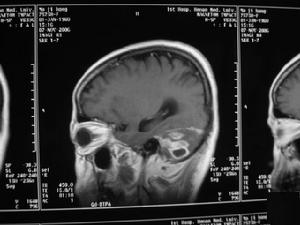

2.顱腦CT掃描 腦膿腫的CT表現依膿腫發展階段而異。急性化膿性腦炎階段 病灶表現為邊界模糊的低密度區 不強化。化膿與膿腫壁形成期,在低密度區周圍可顯示等密度膿腫壁 膿腫壁可輕度強化,強化厚度多不均勻,膿腫較小時,可呈結節狀強化,強化厚度多不均勻,膿腫較小可呈結節狀強化 膿腫周圍有不規則腦水腫帶,多較顯著 CT不僅可以確定膿腫的存在、位置、大小、數目、形狀及其周圍腦組織水腫情況 而且可幫助選擇治療方法和確定手術時機。

3.MRI檢查 MRI檢查有其獨到的優點 不僅在膿腫形成期,於T2加權圖像上能顯示壞死區周圍的屬特徵性的低信號帶,而且在腦炎期也能根據T1和T2弛豫時間的變化,做出早期診斷。即在T1加權圖像上可見白質內不規則的略低信號區 在T2加權圖像上呈明顯的高信號,腦炎中心區為稍低信號,並有占位效應。若採用Gd-DTPA增強,則在T2加權圖像上可以看到不規則的瀰漫性強化,並有助於臨床治療上的參考。